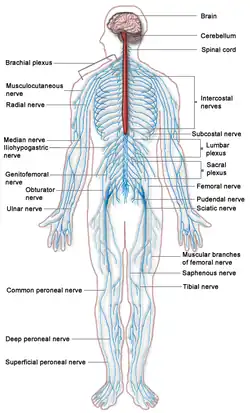

Nervous system

The nervous system consists of the body's neurons and glial cells, which together form the nerves, ganglia and gray matter, which in turn form the brain and related structures. The brain is the organ of thought, emotion, memory, and sensory processing; it serves many aspects of communication and controls various systems and functions. The special senses consist of vision, hearing, taste, and smell. The eyes, ears, tongue, and nose gather information about the body's environment.[36]

From a structural perspective, the nervous system is typically subdivided into two component parts: the central nervous system (CNS), composed of the brain and the spinal cord; and the peripheral nervous system (PNS), composed of the nerves and ganglia outside the brain and spinal cord. The CNS is mostly responsible for organizing motion, processing sensory information, thought, memory, cognition and other such functions.[37] It remains a matter of some debate whether the CNS directly gives rise to consciousness. The peripheral nervous system (PNS) is mostly responsible for gathering information with sensory neurons and directing body movements with motor neurons.[37]

From a functional perspective, the nervous system is again typically divided into two component parts: the somatic nervous system (SNS) and the autonomic nervous system (ANS). The SNS is involved in voluntary functions like speaking and sensory processes. The ANS is involved in involuntary processes, such as digestion and regulating blood pressure.[38]

The nervous system is subject to many different diseases. In epilepsy, abnormal electrical activity in the brain can cause seizures. In multiple sclerosis, the immune system attacks the nerve linings, damaging the nerves' ability to transmit signals. Amyotrophic lateral sclerosis (ALS), also known as Lou Gehrig's disease, is a motor neuron disease which gradually reduces movement in patients. There are also many other diseases of the nervous system.[37]